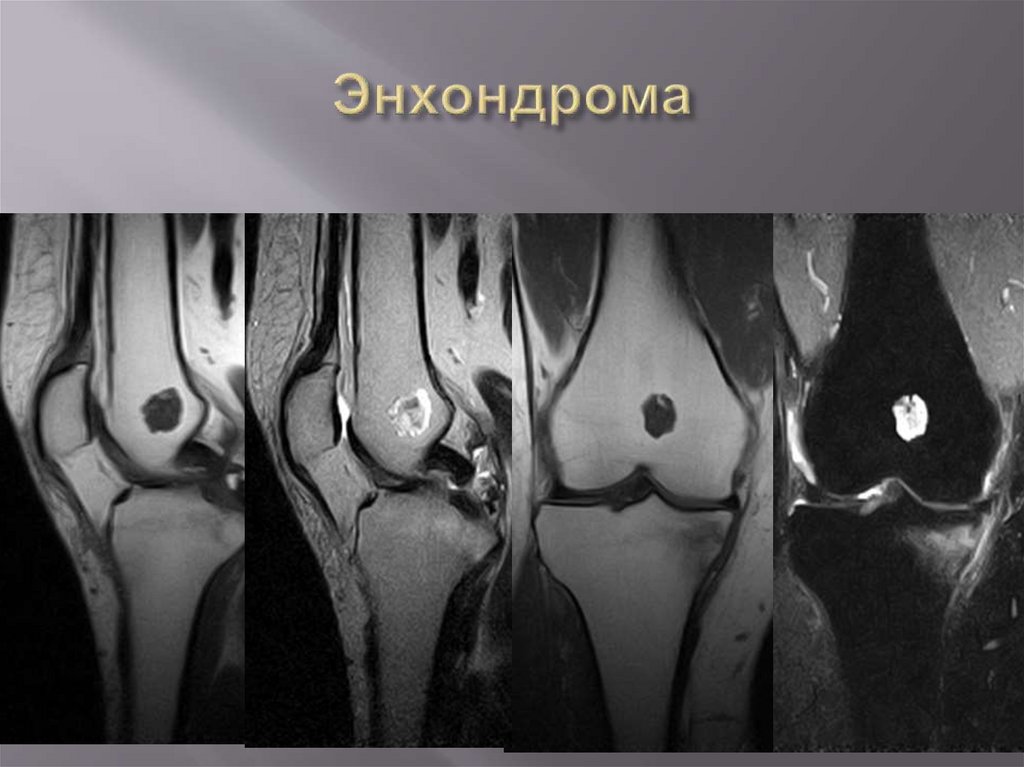

Синовиальный

хондроматоз